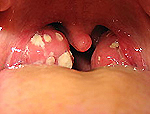

Enlarged, red tonsils and oxidative white patches of tonsillitis - - Wikipedia photo

When Aaron Kelly gave his performance in the fourth position host Ryan Seacrest queried him about hearing that he was also sick. Kelly went on to explain that he had laryngitis and tonsillitis. He also noted that it was going around but didn't specify if it was going around with other contestants or around in general.